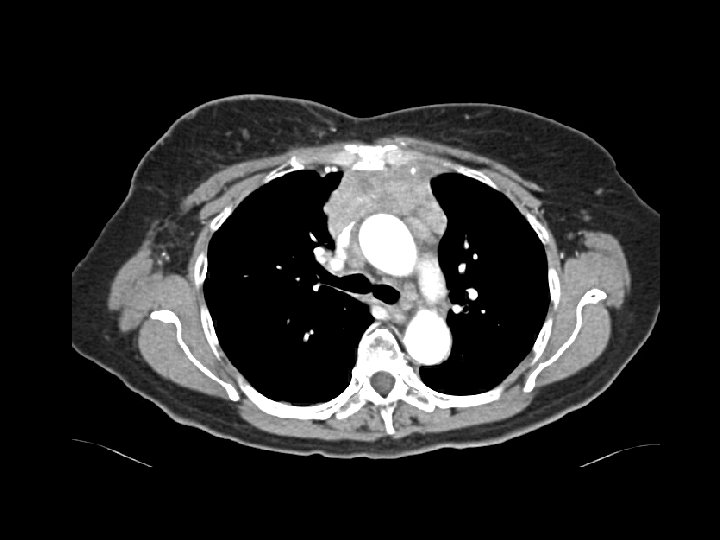

Metastatic germ cell tumor • Findings: – left neck soft tissue mass – pulmonary nodules – large retroperitoneal mass with speckled calcifications • ddx: – lymphoma